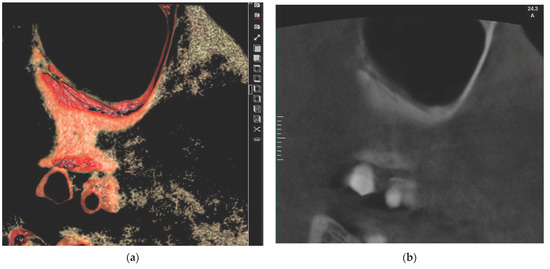

The aim of this study is to evaluate anatomical considerations and assess the volume of the maxillary sinus bone graft. There were sixty-three patients (eighty-three sinuses) who had taken CT scans for implant surgery. Patients included those whose height of the residual alveolar [...] Read more.

The aim of this study is to evaluate anatomical considerations and assess the volume of the maxillary sinus bone graft. There were sixty-three patients (eighty-three sinuses) who had taken CT scans for implant surgery. Patients included those whose height of the residual alveolar bone was less than 5 mm. The position of posterior superior alveolar artery, the thickness of the maxillary sinus wall, and the volume of the maxillary sinus according to the amount of sinus floor elevation were measured. The mean vertical distance of posterior superior alveolar artery was 11.91 ± 4.79 mm from 3.03 mm to 24.05 mm. The mean thickness of the lateral wall was 1.71 ± 0.55 mm in the range of 0.74 mm to 3.93 mm. The volume of 3 mm, 5 mm, 7 mm, and 10 mm from the sinus floor was 0.173 ± 0.11 cm3, 0.526 ± 0.25 cm3, 1.068 ± 0.43 cm3, and 2.184 ± 0.74 cm3 on average, respectively. The knowledge of the posterior superior alveolar artery position, the lateral wall thickness, and the volume of the maxillary sinus can help the clinician for sinus bone graft. Full article